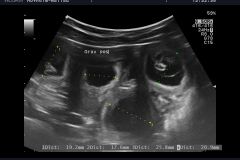

Wir haben tolle Neuigkeiten, Happy ist trächtig. Wir waren heute zum Ultraschall und laut Tierarzt, können wir uns über einen großen Wurf freuen.